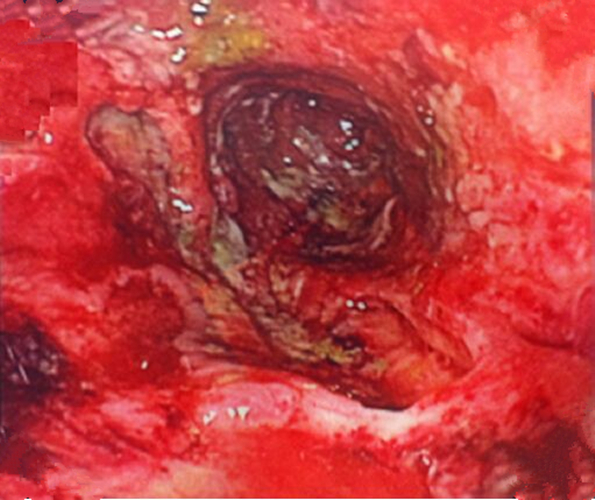

纖維結腸鏡檢查

慢性結腸炎圖片

嚴重慢性結腸炎的

嚴重慢性結腸炎腐爛的